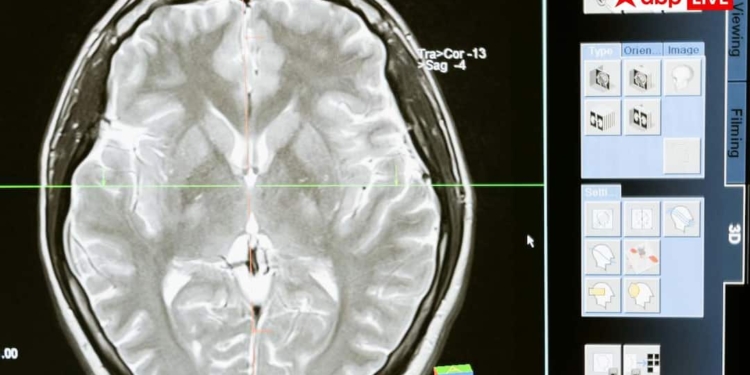

न्यूरोलॉजिस्ट की मानें, तो जब बच्चों में दौरे पड़ने के कारणों की जांच की गई और उनके दिमाग का स्कैन किया गया, तो दौरे पड़ने की मुख्य वजह पैरासाइटिक इंफेक्शन या दिमाग में मौजूद कीड़े पाए गए. इसके बारे में जानना हर किसी के लिए जरूरी है कि कैसे पैरासाइटिक इंफेक्शन बच्चों में दौरे पड़ने का मुख्य कारण बन रहा है.

दिमाग में पैरासाइटिक इंफेक्शन की मुख्य वजह न्यूरोसिस्टिकोसिस नाम की स्थिति है. यह एक ऐसी स्थिति है, जिसमें हमारे दिमाग में सूअर के फीताकृमि, जिन्हें हम पोर्क टैपवार्म भी कहते हैं, उनके अंडों के कारण यह समस्या होती है. ये अंडे कहीं भी हो सकते हैं, जैसे मिट्टी में, गंदे खाने में या किसी पत्तेदार सब्जियों के बीच में. इनके सेवन से ये अंडे हमारे खून के माध्यम से सीधे दिमाग में चले जाते हैं और वहां जम जाते हैं. ध्यान देने वाली बात यह है कि ये कीड़े नहीं होते, बल्कि उनके अंडे होते हैं.

न्यूरोसिस्टिकोसिस में दौरे पड़ने का सबसे बड़ा कारण यह है कि दिमाग इन अंडों से बचने के लिए कई तरह की प्रतिक्रिया करता है. जब ये अंडे दिमाग में पहुंच जाते हैं, तो हमारा शरीर उनके चारों तरफ सूजन पैदा कर देता है, ताकि बाहरी खतरों को एक जगह रोका जा सके. इसी सूजन की वजह से हमारे दिमाग की कोशिकाओं के बिजली के सिग्नल यानी इलेक्ट्रिकल सिग्नल में गड़बड़ी पैदा हो जाती है, जो दौरे पड़ने का कारण बनती है. जैसे-जैसे यह अंडा दिमाग में सड़ना शुरू करता है, वैसे-वैसे कई तरह की दिक्कतें होने लगती हैं, जिनमें सिरदर्द और दौरे पड़ना शामिल है.